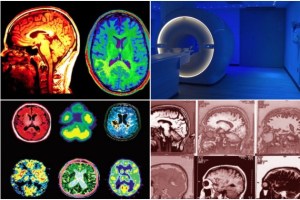

Χάρη όμως στις νέες νευροαπεικονιστικές τεχνικές (τομογραφία εκπομπής ποζιτρονίων, λειτουργική μαγνητική τομογραφία κ.ά.), είναι πλέον εφικτός ο εντοπισμός και η ανάλυση των εγκεφαλικών δομών που εμπλέκονται και τελικά παράγουν την ανθρώπινη σκέψη.

Ετσι, τη δεκαετία του 1980, θα κάνει την εμφάνισή της η Μαγνητική Τομογραφία (MRI), μια πραγματικά μη επεμβατική τεχνική απεικόνισης των εγκεφαλικών δομών που διαθέτοντας μεγαλύτερη διακριτική ικανότητα από την αξονική τομογραφία μπορεί να αποκαλύπτει πιστότερα τις μικροδομές του εγκεφάλου, συμβάλλοντας αποφασιστικά στην ανατομική χαρτογράφησή τους.

Ομως, η πιο πρόσφατη και πιο ισχυρή τεχνική απεικόνισης των εγκεφαλικών λειτουργιών είναι η λεγόμενη Λειτουργική Μαγνητική Τομογραφία (fMRI), η οποία από τα τέλη του εικοστού αιώνα έχει αποδειχτεί το παντοδύναμο και σχεδόν «μαγικό» εργαλείο για τη διερεύνηση των περισσότερων εγκεφαλικών λειτουργιών.

Σε αυτή την παραλλαγή της μαγνητικής τομογραφίας (MRI), ο σαρωτής, δημιουργώντας ισχυρά μαγνητικά πεδία, ανιχνεύει τις ελάχιστες αλλαγές στον μεταβολισμό του οξυγόνου που μεταφέρεται από το αίμα στους νευρώνες των επιμέρους δομών του εγκεφάλου.

Σε σύγκριση με άλλες τεχνικές, η fMRI είναι η λιγότερο επεμβατική αφού δεν απαιτεί καμία έκθεση σε ραδιενεργές ουσίες ή υψηλές ακτινοβολίες και παρουσιάζει πολύ μεγαλύτερη διακριτική ικανότητα.

Γεγονός που την καθιστά εξαιρετικά χρήσιμη τεχνική στη μελέτη ακόμη και των πιο πολύπλοκων και αφηρημένων νοητικών λειτουργιών, επιτρέποντας πρώτη φορά τον εντοπισμό και την οπτικοποίησή τους.